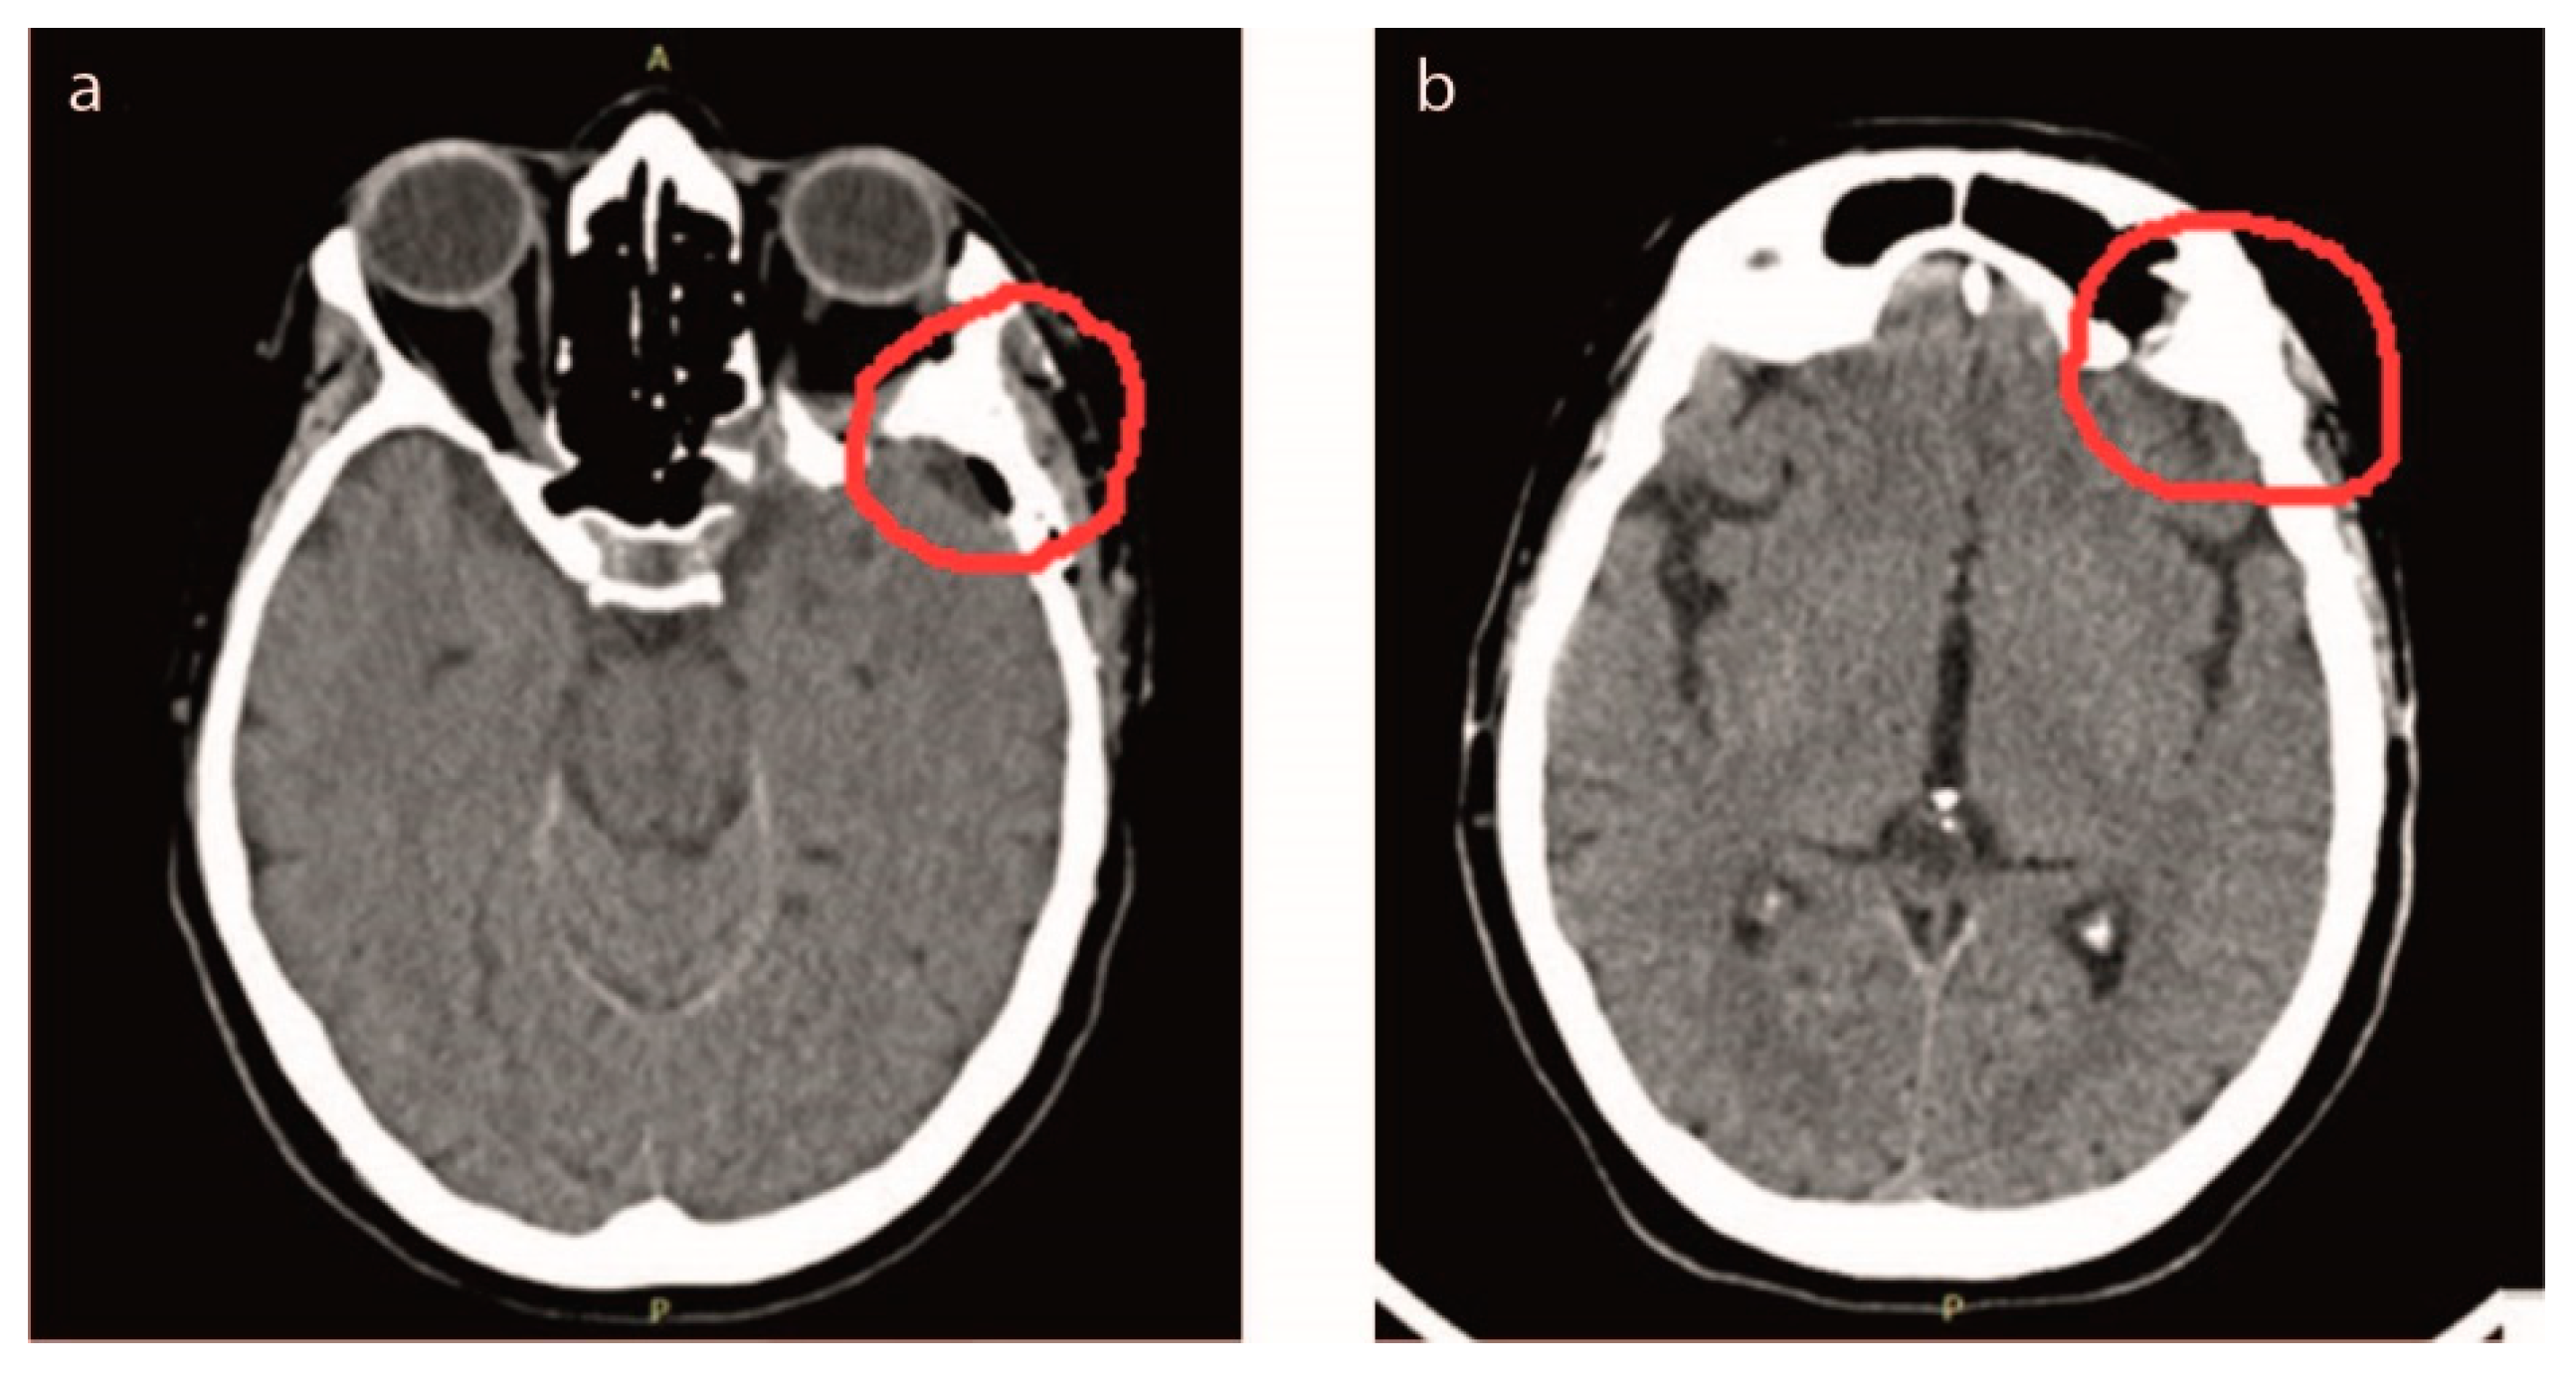

- Case #5: The fifth patient, 65-year-old female, showed a meningioma tumor located at the back of the right eye, diagnosed by CT (Figure 1e). The tumor included temporal and sphenoid bone in the skull. The surgical operation involved the removal of the tumor as well as part of two bones, which were rebuilt with custom-made SBoD grafts (Figure S3 in Supplementary Materail). CT was used to design surgery, both in terms of tumor rescission and further bone reconstruction. Given the wide extension of the tumor mass, a significant portion of bone had to be removed, and custom-made SB was provided in pieces, which were assembled during surgery, bed-side, and soaked into blood before grafting, to accelerate the osteointegration process [35]. Once placed, the complete graft has been stabilized with two small titanium plates (KLS-Martin, Germany).

- Case #5: After 11 days post-surgery a CT was performed to check the complete removal of the tumor and that the SB was integrating without causing foreign body reaction or inflammation. After 2 years post-surgery, osteointegration was fully successful, with the reconstruction of the temporal and sphenoid bone. The bone was perfectly regenerated, and the patient’s cranial anatomy was completely reconstructed (Figure 5e). When we compared the two regions of interest in the post-surgery CT, we observed that the second one included a greater amount of bone. The bone was grown not only within the SB plaque but it was also remodeled to restore the correct skull anatomy; as a result, the right and left sides were symmetrical.